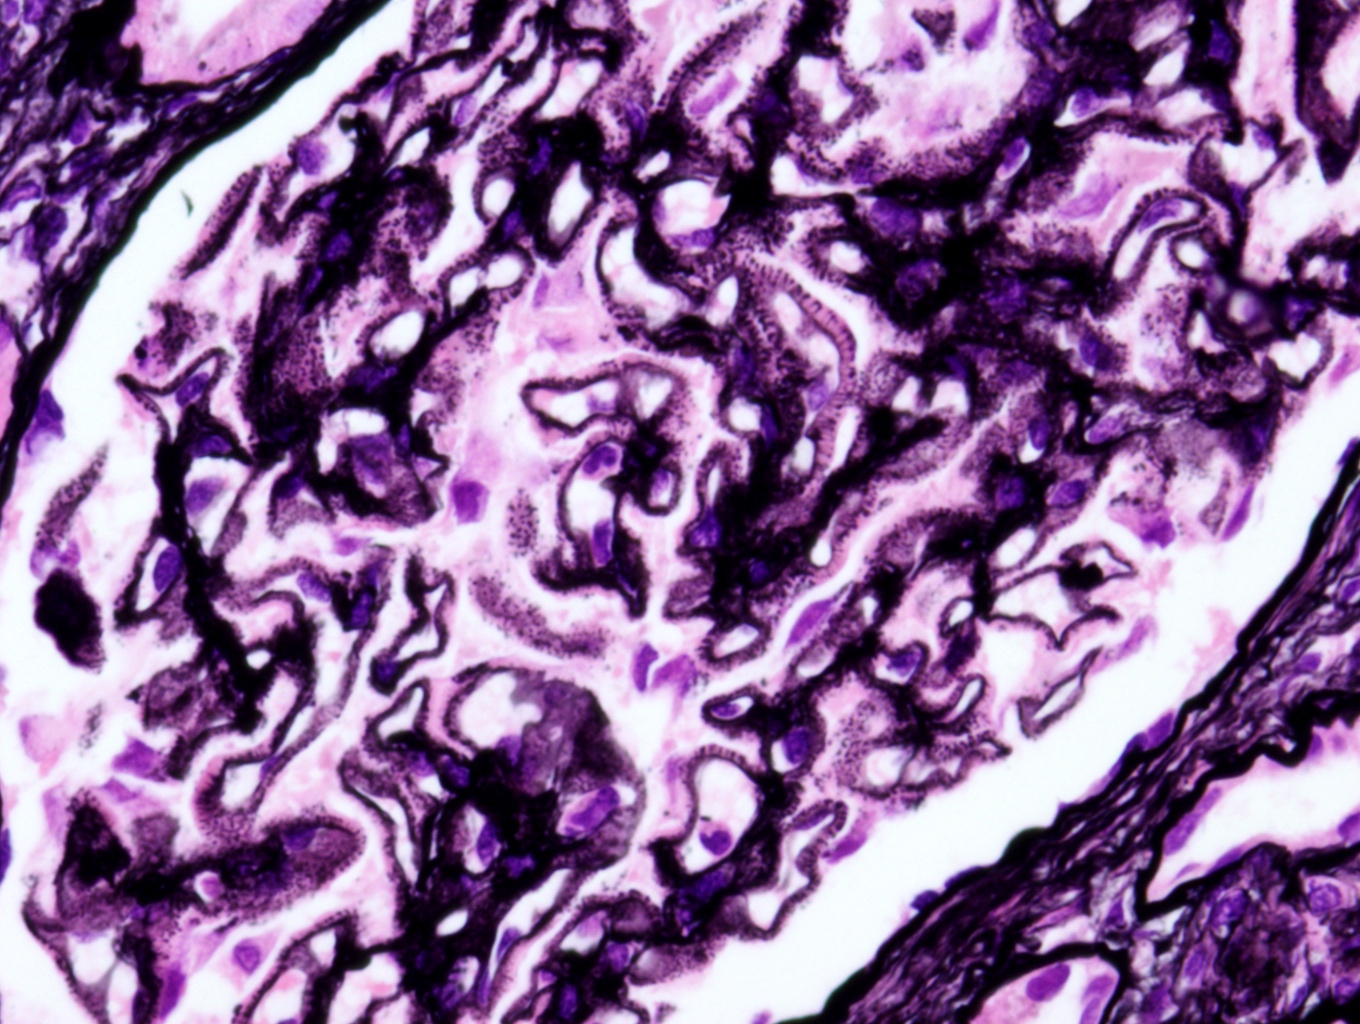

- Thickening of glomerular basement membrane and subepithelial deposition of immune complexes (silver stain, spike)

Microscopic (histologic) description

- Thickening of glomerular basement membrane

- Subepithelial spike formation or vacuolated appearance on PAS or Jones silver stain (Colvin: Diagnostic Pathology - Kidney Diseases, 2nd Edition, 2015, Zhou: Silva's Diagnostic Renal Pathology, 2nd Edition, 2017)

Microscopic (histologic) images

- Microscopic description: 18 glomeruli, 1 of these with global sclerosis. Thickening of the glomerular capillary wall. Presence of spikes and internal vacuolizations of the glomerular basement membrane evaluated by silver stain. No evidence of hypercellularity, crescent or necrosis. Fibrosis occupying < 10% of the interstitium.